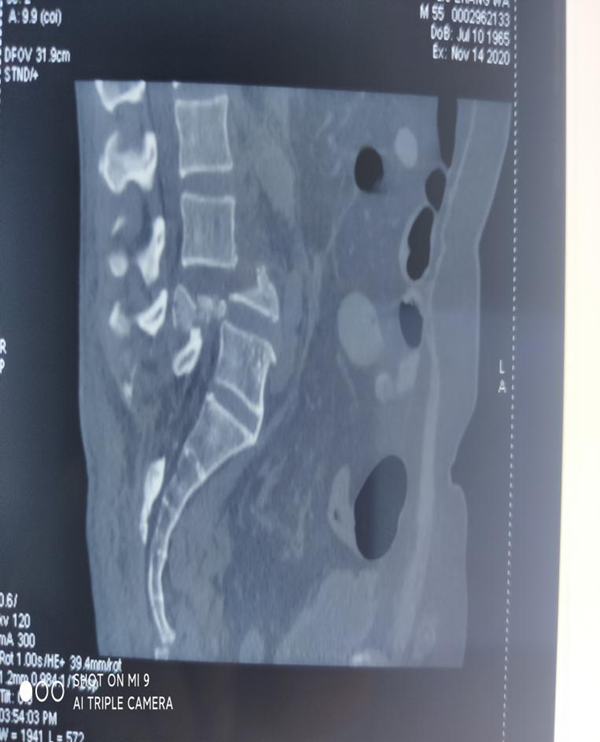

刘某家属找到了我院骨三科的张纯教授。张教授经过详细了解患者的病情,并判断这是一例严重复杂的脊髓损伤,需要立马进行手术治疗。于是为刘某联系了病房,结合患者年龄大、手术创伤大、出血风险高等特点,经过多次科室讨论及多科室疑难病例会诊,积极联合危重医学科、麻醉科、输血科等相关科室共同制定了周密的手术方案。根据患者病情制定了详细的手术计划及围手术期治疗方案。经过严密的手术前准备,以张纯主任医师为主刀、王伟卓主治医师和黄思华博士为助手,吴刚副主任医师、罗斌医师为麻醉医师,殷敏、马霞为配合护士,黄亚娟、王芳医师为术中诱发电位监护医师的手术团队努力下,手术顺利完成,切开复位内固定保护了严重受伤的脊髓,并进行了脊柱的重建。

尽管手术非常顺利,但是由于患者病情严重,经历大手术打击后的系列问题带给骨三科医护们诸多的挑战,如循环支持,呼吸支持、气道管理、补液、营养、预防院内感染、呼吸机撤离、拔除人工气道……

术后第二天,经过在骨三科近二十个小时的精心治疗后,患者循环、呼吸逐步稳定。顺利撤离呼吸机支持,在对症状进行了详尽评估后撤除监护。接下来的术后康复问题,又成了重中之重,由于伤口疼痛,心理压力大,患肢不便等存在不少问题,经康复科和骨三科的各位医护帮助下,刘某和家属终于露出了术后的第一次笑容。目前患者恢复良好,很快下肢感觉、肌力恢复,现患者正在康复中。